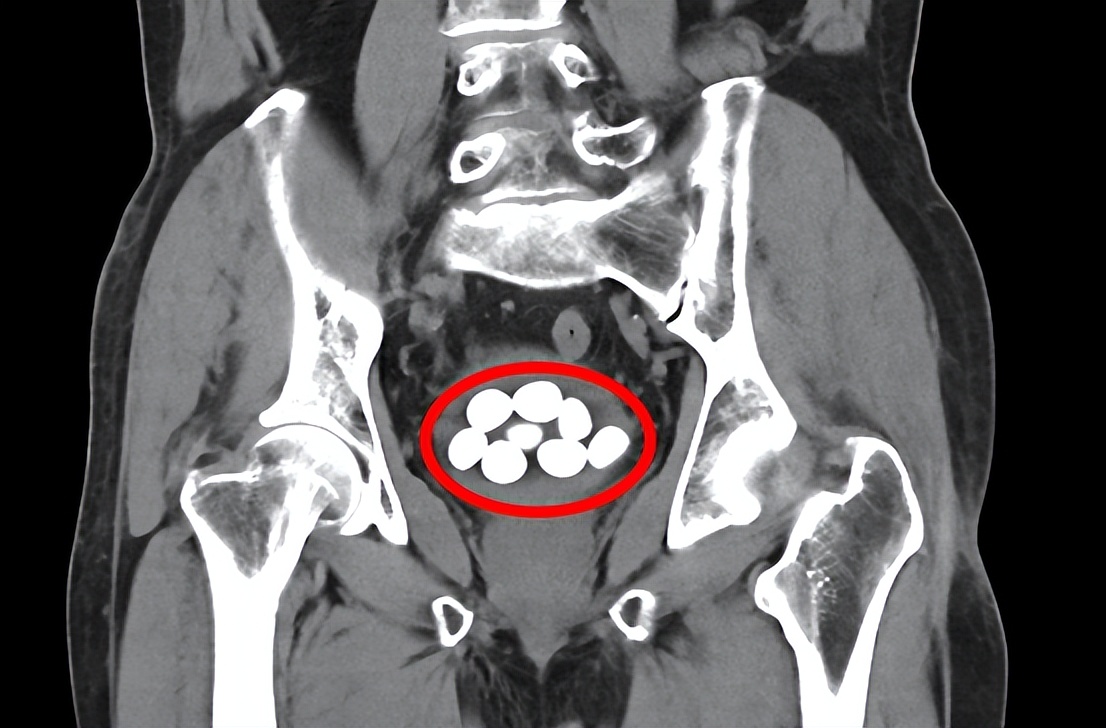

85岁老人9颗膀胱结石分别击碎取出

平南县第二人民医院泌尿外科为一位85岁老人成功实施经尿道膀胱结石碎石术和前列腺电切手术,将9颗膀胱结石分别击碎取出,解除了老人的病痛之苦。整个手术持续近2个多小时,术 后第四天 ,经泌尿外科专科护理团队的精心护理,患者顺利出院。